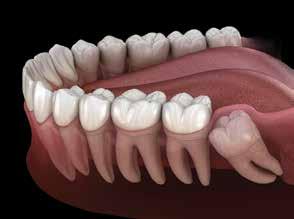

Do I really need to remove my wisdom teeth, they don’t hurt?

Through the studies of ancient tribes there was a time where one’s jaws were big enough to accommodate 32 teeth. Through environment and dietary changes we no longer have room for the third set of molars, also called wisdom teeth. When these teeth cannot erupt in to the mouth correctly they often become “impacted” or stuck in a crooked position. This impaction causes several problems which are not always painful including:

• Alignment: the third molars can cause crowding and create the need for orthodontics to straighten teeth for a healthy smile

Wisdom Teeth: Is it wise to keep them?

Wisdom teeth or third molars are the last permanent molars to erupt in the mouth. They usually appear between the ages of 17 to 25 but can grow any time after that. We don’t usually use those teeth for chewing because they are so far back in the mouth. Third molars are hard to keep clean and very prone to decay.

Misaligned wisdom tooth that caused patient to lose both teeth. Impacted Wisdom teeth.